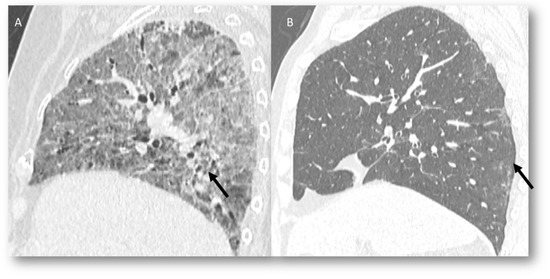

| Type of Pneumonia | Lung Involvement | CT-Patter | Mechanisms of Lung Radiation Damage |

|---|---|---|---|

| RRP | Target area | Ground-glass opacities and consolidative opacities. | Unknown (A non-immune fixed drug reaction-like condition, dysregulated release of reactive oxygen species, abnormalities of tissue vasculature and impaired DNA repair). |

| RP | Target area | Ground-glass opacities and consolidative opacities. | Direct damage to the DNA and indirect damage through the production of reactive oxygen species (ROS), causing changes in vascularity and capillary permeability, activation of the inflammatory response and alteration of immunological response |

| ICI-related pneumonitis | Diffuse (related to the phase of disease) | Ground-glass and reticular opacities; consolidative opacities; interlobular septal thickening; “crazy-paving” pattern | Autoimmune |

| COVID-19 pneumonia | Diffuse (related to the phase of disease) | Ground-glass opacities; crazy-paving pattern; consolidative opacities; interlobular septal thickening (according to the phase of disease) | Unknown, supposed cytokine storms |

| Pulmonary lymphangitis carcinomatosa | Diffuse (related to the phase of disease) | Irregularly interlobular septal thickening; smooth (early stage) or nodular thickening (late development); ground-glass opacities; pleural effusions. | Tumor spread through lymphatic vessels |